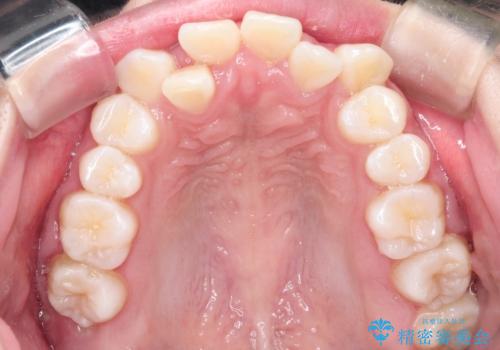

八重歯を改善!美しい口元を実現するハーフリンガル矯正

- 前歯のガタツキと口元のコンプレックスを解消するために来院されました。

ハーフリンガル矯正は、見た目を気にせずに矯正治療ができる方法です。この治療法は、八重歯や前歯のガタツキを効果的に改善します。特徴として、ワイヤーが上の歯の裏側に装着されるため、装置が外から見えません。これにより、治療中も自然な笑顔を保ちながら安心して治療を続けることができます。歯並びの悩みを持つ方にとって、非常に魅力的な選択肢です。